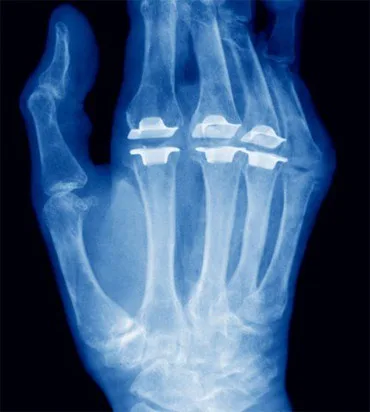

Che la vitamina D faccia bene alle ossa e che un deficit di questa sostanza sia correlato a varie patologie autoimmuni, tra cui l’artrite reumatoide, si sa. E non è una novità nemmeno che il grado di esposizione al sole giochi un ruolo fondamentale nell’influenzare la concentrazione di vitamina D nell’organismo, e dunque nel modulare l’assorbimento di calcio nelle ossa. Quello che invece appare inaspettato è che nel Mezzogiorno le persone affette da artrite reumatoide sarebbero più carenti in vitamina D rispetto a quelle di altre regioni italiane, almeno nel periodo primaverile.

A dimostrarlo, un studio multicentrico su 581 pazienti in 22 centri equamente distribuiti in tutta Italia presentato dal Prof. Orsolini in occasione del XLVIII Congresso Nazionale della Società Italiana di Reumatologia (Rimini, 23-26 novembre 2011) e realizzato dal Gruppo SIR per lo Studio dell’Osteoporosi e delle Malattie Metaboliche dello Scheletro. E non solo: nonostante l’Italia abbia una posizione geografica favorevole rispetto ad altri Paesi Europei (in altri termini, ci sia molto sole), si rileverebbe una prevalenza di insufficienza di Vitamina D superiore alla media europea, se si considerano i Paesi alla stessa latitudine.